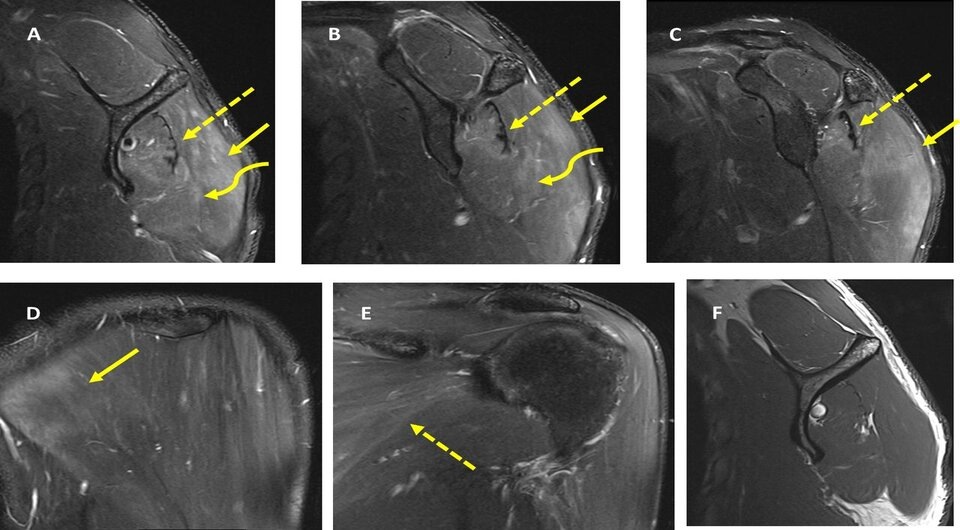

Filippo Gerber et al. / BMJ Case Reports, 2024

Синдром Персонажа — Тернера, или невралгическая амиотрофия, — это редкая периферическая патология нервов с острой сильной болью в плече, слабостью и атрофией мышц плечевого пояса и мышц предплечья. Среди факторов риска выделяют, в том числе, инфекционные: описаны случаи развития синдрома при заражении коронавирусом, парвовирусом и вирусами оспы. Осмотр показал атрофию дельтовидных, трехглавых и двуглавых мышц левого плеча и предплечья. Мышечная сила и рефлексы этих и соседних мышц были снижены. Последующие магнитно-резонансные томографии и электромиографии мышц левого надплечья, плеча и предплечья навели врачей на диагноз невралгическая амиотрофия. Реабилитация с применением физиотерапии позволила облегчить боль и вернуть мышечную силу в левой верхней конечности.